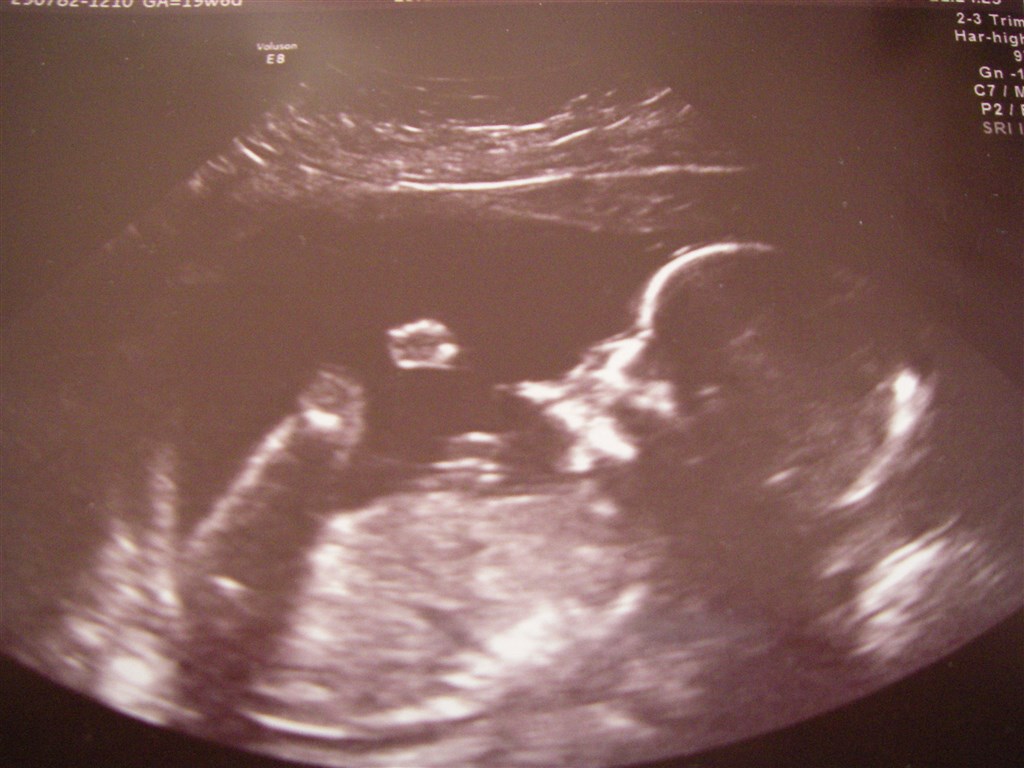

En god dag lakker mod ende, vi var til MD scanning hvor vi så en meget livlig fin baby, så livlig at hun opgav at lave et 3D billed

Og jeg fik ret i min fornemmelse af kønnet, vi venter en dreng

Vedhæftede fotos (klik for at se i fuld størrelse)